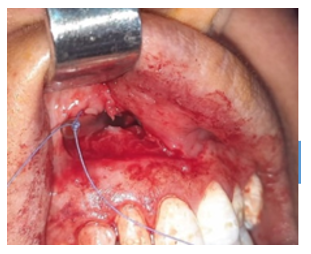

A cone beam CT scan (CBCT) confirmed a well-defined hypodense lesion in the maxillary region. The vestibular cortical bone was displaced and ruptured in several areas, with evidence of compromised integrity of the nasal and sinus floor (Figure 2).

Figure 2 CBCT scan showing rupture of the vestibular cortical and the nasal floor.